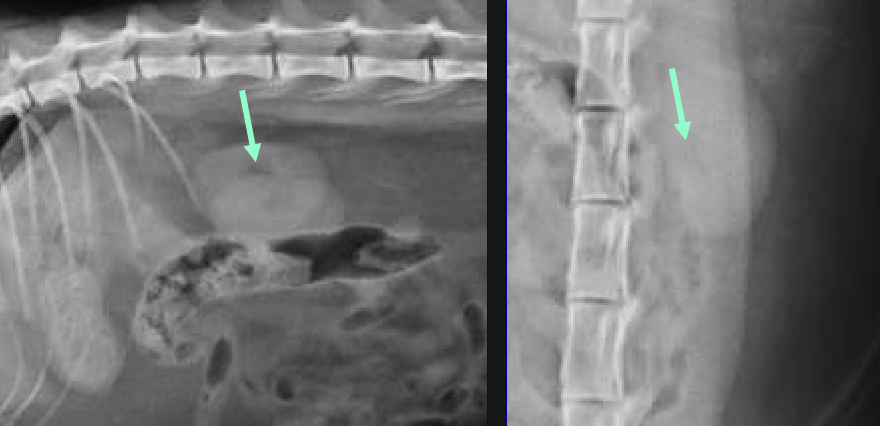

space between dorsal margin of the parietal peritoneum and the abdominal wall

hypaxial muscles and kidneys

retroperitoneal structures

Hypaxial muscles

kidneys